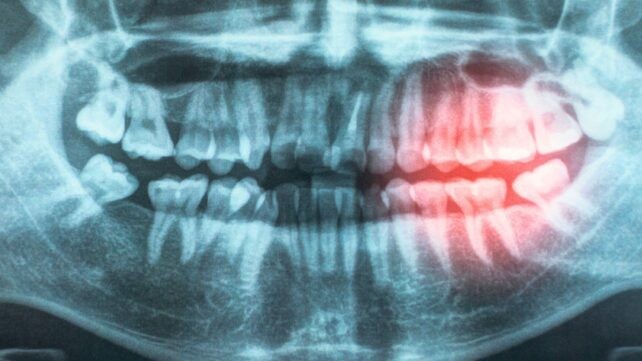

Przegląd przygotowany przez Komisję ds. Prewencji Chorób Sercowo‑Naczyniowych Amerykańskiego Towarzystwa Serca wzmacnia tezę, że utrzymanie zdrowych dziąseł pomaga chronić przed chorobami serca. Oparłszy swoje ustalenia na dekadzie literatury obejmującej badania genetyczne, badania kliniczne i testy laboratoryjne, raport ten aktualizuje swoje oświadczenie naukowe z 2012 roku, dostarczając jeszcze mocniejszych dowodów na to, że choroba serca wywołana miażdżycą tętnic (ASCVD) jest ściśle związana z chorobą przyzębia. W ramach przeglądu naukowcy rozważali możliwe powody powiązania, w tym prawdopodobieństwo, że bakterie dostają się do organizmu przez uszkodzone dziąsła, przyczyniając się do przewlekłego zapalenia. „Twoje usta i twoje serce są połączone” — mówi kardiolog dziecięcy Andrew Tran. „Choroba dziąseł i złe higieniczne nawyki w jamie ustnej mogą pozwolić bakteriom na dostanie się do krwiobiegu, powodując stan zapalny, który może uszkadzać naczynia krwionośne i zwiększać ryzyko chorób serca.” ASCVD pozostaje główną przyczyną zgonów na świecie, a jeśli poprawa higieny jamy ustnej mogłaby być jednym ze sposobów powstrzymania tego zjawiska, to warto to badać. W analizowanych badaniach obejmujących również dzieciństwo stwierdzono, że dbanie o zęby od młodego wieku mogłoby obniżyć ryzyko problemów sercowych w późniejszym życiu. „Istnieją mocne dowody na to, że leczenie choroby przyzębia poprawia pośrednie miary wyników, takie jak ciśnienie krwi, poziom cholesterolu HDL i markery zapalne,” piszą naukowcy w opublikowanej pracy. „To ważne odkrycie, ponieważ te miary wyników są znane z tego, że zwiększają przyszłe ryzyko chorób serca i stanowią możliwy związek między chorobą dziąseł a ASCVD.”

Przegląd oparty na dziesięcioletniej literaturze obejmującej badania genetyczne, próby kliniczne i testy laboratoryjne wskazuje, że choroba serca wywołana miażdżycą tętnic (ASCVD) jest ściśle powiązana z chorobą dziąseł. ASCVD pozostaje największą przyczyną zgonów na świecie, a nowe dowody sugerują, że istnieje niezależny związek między tymi warunkami, nawet po uwzględnieniu innych czynników ryzyka takich jak palenie, wiek i otyłość. Badania z różnych populacji sugerują spójne wyniki, potwierdzając, że powiązanie to nie zależy jedynie od wspólnych czynników ryzyka.

Naukowcy rozważają możliwe mechanizmy powiązania choroby dziąseł z chorobą serca. Jednym z kluczowych scenariuszy jest to, że bakterie mogą dostawać się do krwiobiegu przez uszkodzone dziąsła, wywołując przewlekłe zapalenie, które uszkadza naczynia krwionośne i sprzyja rozwojowi ASCVD. Jednym z wyzwań pozostaje fakt, że wiele czynników ryzyka — od palenia po starzenie się i otyłość — zwiększa prawdopodobieństwo wystąpienia obu stanów. Jednak nowe dowody sugerują istnienie niezależnego powiązania między chorobą dziąseł a ASCVD, co skłania do poszukiwania mechanizmów odpowiadających za tę zależność.